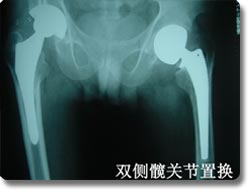

关节置换可以说是本世纪骨科手术最伟大的突破之一。目前它已应用於治疗肩关节、肘关节.腕关节、指间关节 、髋关节、膝关节及踝关节等疾患,但以全人工髋关节及膝关节置换最为普遍。对骨关节炎、股骨头无菌性坏死、老年性股骨颈骨折等疾病具有明显治疗效果,我科目前已开展各种置换手术800余例,疗效受到患者普遍肯定。 |